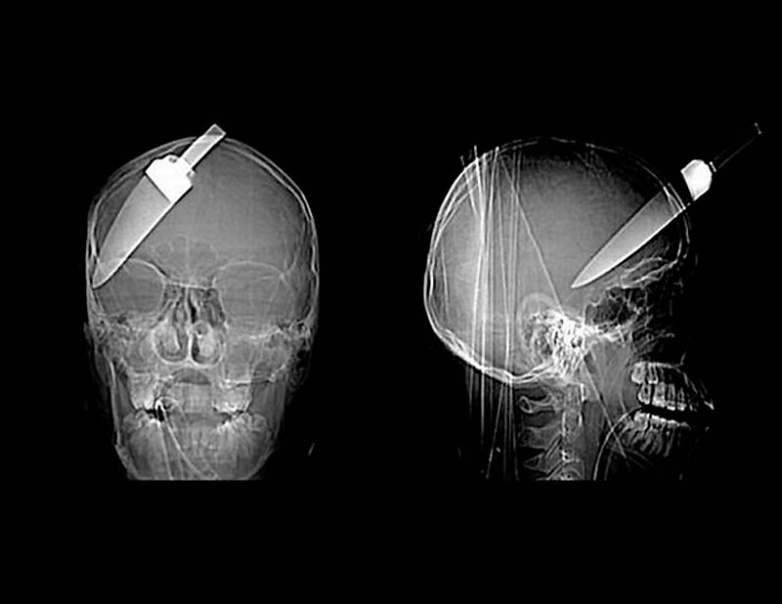

15. Нож в голове 10-летнего мальчика. Мальчик выжил.

18. 12-сантиметровый нож в черепе подростка.